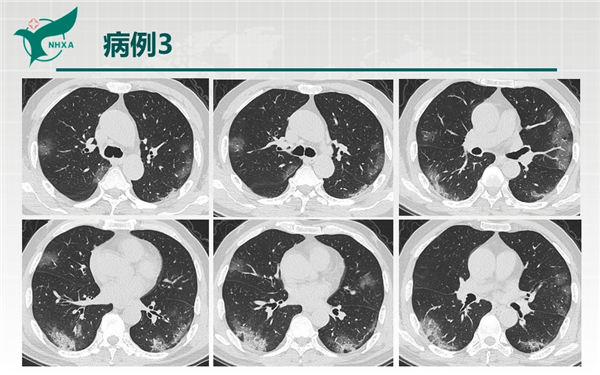

【病例分享】新型冠狀病毒肺炎3例(西安市第九醫(yī)院)

幻燈片6.jpg